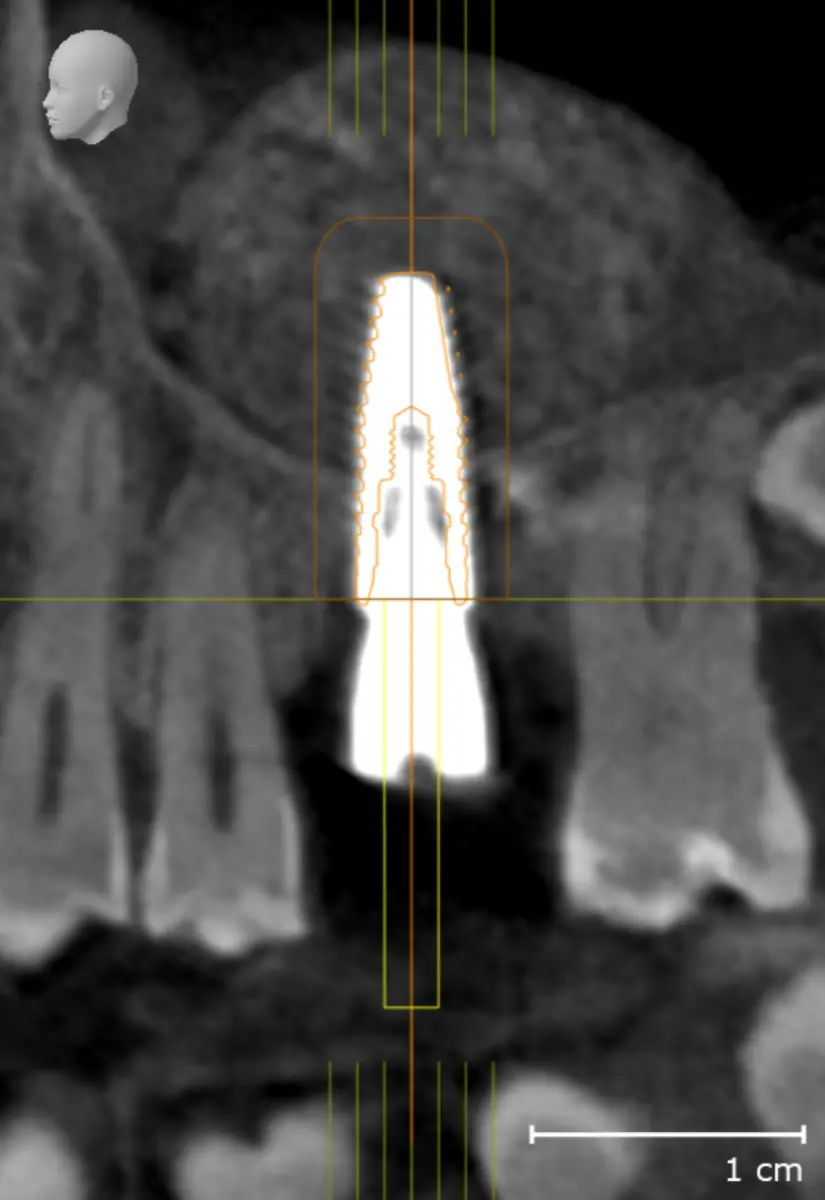

Elevación del seno maxilar

La elevación de seno maxilar permite aumentar el hueso en la zona posterior del maxilar superior cuando no hay suficiente altura para colocar implantes. Al elevar el suelo del seno maxilar y añadir hueso autólogo o xenoinjerto, se consigue una base ósea sólida que garantiza la estabilidad y el éxito de los implantes dentales.